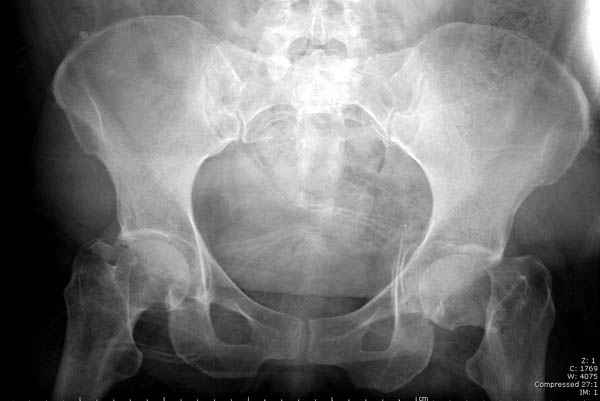

Мы сейчас наблюдаем больную с похожим состоянием, больной 54, после автоаварии, со множественными

переломами скелета.

Состояние осложнена черепномозговой и абдоминальной травмой, переломы L2-5, челюстно-лицевые переломы и состояние после транспланта почки.

Перелом шейки смогли зафиксировать через пару дней, ацетабулум до сих пор не оперирован, на вытяжении.

Из-за упущенного времени (три недели с момента

поступления) ацетабулум ведем консервативно.

На снимке ацетабулума редко встречающийся очень низкий перелом, наверное, трудно было репозицию через один доступ? Перелом как бы замкнулся в квадрилатеральной поврехности.